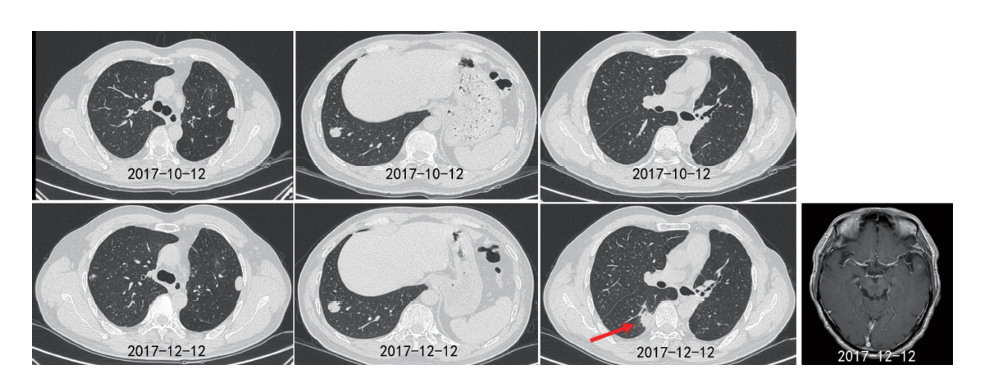

患者于2017-12-22开始口服吉非替尼, 1个月后复查提示双肺结节及左颞叶病灶明显缩小(见图3), 疗效评价SD(-23%), 后续定期复查, 病灶继续缩小, 最佳疗效PR(-74%)。